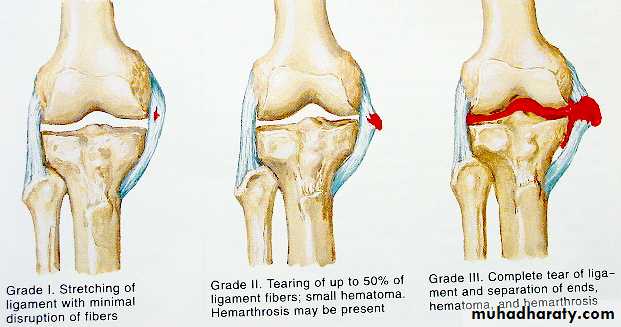

Ligament injuries

Sprain : stretching of ligament but it is still anatomically intact

Partial tear : more pain, joint is stable

Complete tear : less pain , joint unstable

Tx : partial immobilize & exercise

complete surgical repair